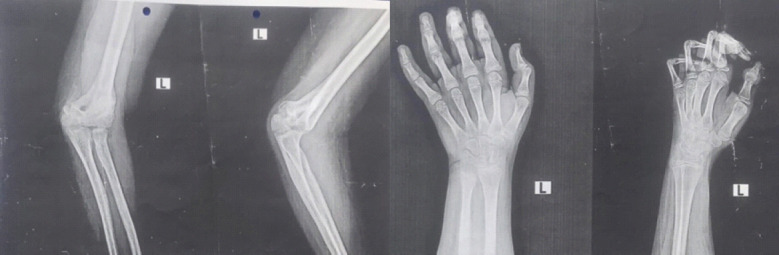

Case report: We report a case of 14-year-old boy with fingers flexion contracture, decreased hand mobility and pain on his left hand. He had a history of left forearm fracture and that was treated by a traditional bonesetter with herbs and cardboards 6 months back. Later he started to have pain and deformity of left hand for which they came to the BGS Global Institute of Medical Sciences and diagnosed with VIC and started with antibiotics, analgesics and performed a Max Page operation after thorough work up.